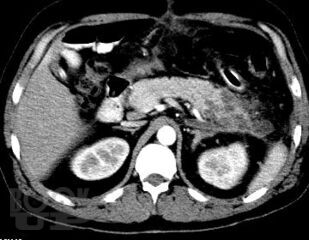

Учебно-методическое пособие посвящено актуальным проблемам этиологии, патогенеза, диагностики, современным методам консервативного и оперативного лечения острого панкреатита Представлены новые классификации, схемы консервативного лечения, современные виды оперативного лечения. Иллюстрировано рисунками, таблицами, имеются тестовые задания и задачи. Пособие предназначено для ординаторов и слушателей дополнительного профессионального образования, обучающихся по специальности 31.08.67 Хирургия.